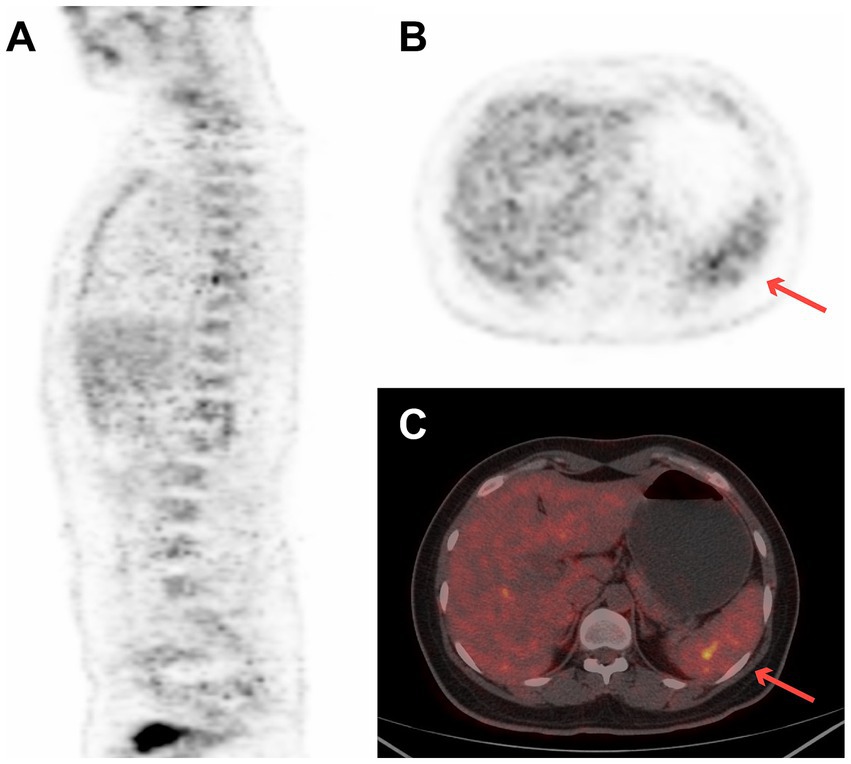

A 27-year-old woman with a 2-week history of back pain was admitted to our orthopedics department. The complete blood count revealed thrombocytopenia (platelet count = 58 × 109/L). Physical examination revealed scattered ecchymosis on the skin. Figure 2 shows images of case 5 with bone marrow and spleen involvement. 18F-FDG PET/CT revealed high FDG-avid lesions of the bones (SUVmax, 9.1, Figure 2A) and spleen (SUVmax, 4.4, Figures 2B,C). No clear lesions were detected at any other sites. This patient underwent a bone marrow examination, and the disease was confirmed as BPDCN. She died of disseminated intravascular coagulation 20 days after diagnosis.

Figure 2

18F-FDG PET/CT images of case 5 revealed high FDG-avid of the spleen (SUVmax 4.4) and bones (SUVmax 9.1). (A) Sagittal PET image of bone, (B) transverse PET image of spleen (red arrow), and (C) transverse fused PET/CT image of spleen (red arrow).